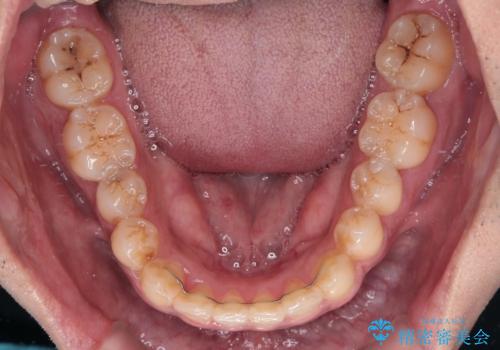

途中2年強の来院がなく、改善されていたデコボコが元に戻ったり、装着時間が不足しており前歯のデコボコは十分に改善することはできませんでしたが、5年間の有効期限内で可能な限り歯列を整えることができました。